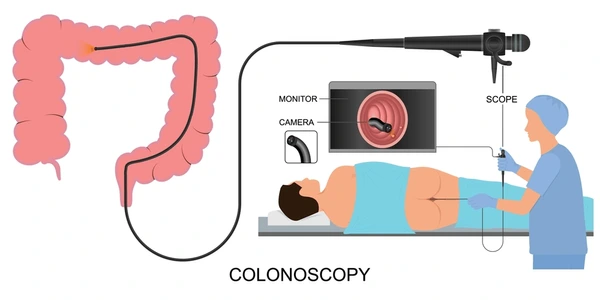

إذا كنت تبحث عن أفضل دكتور منظار بالكويت بخبرة عالية وتشخيص دقيق باستخدام أحدث تقنيات المناظير، فإن الدكتور فهد الإبراهيم يُعد من أبرز الأسماء المميزة في مجال الجهاز الهضمي والمناظير بالكويت.

إذا كنت تفكر في الفحص، من المهم معرفة سعر منظار المعدة في الكويت مع إمكانية المتابعة لدى دكتور فهد الإبراهيم الذي يقدم تقييمًا شاملًا قبل الإجراء.